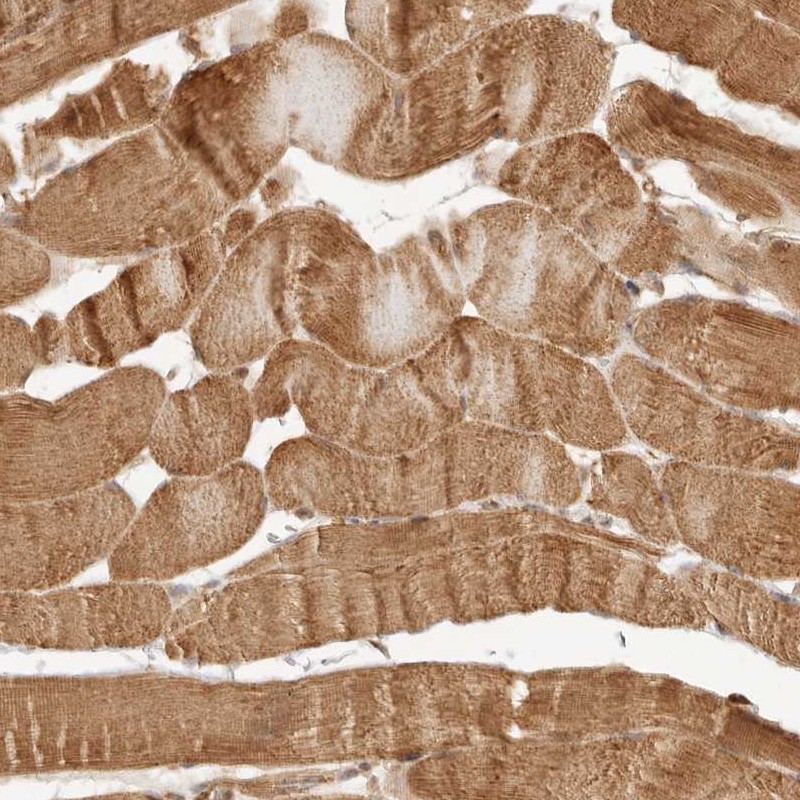

Immunohistochemical staining of human skeletal muscle shows cytoplasmic positivity in myocytes.